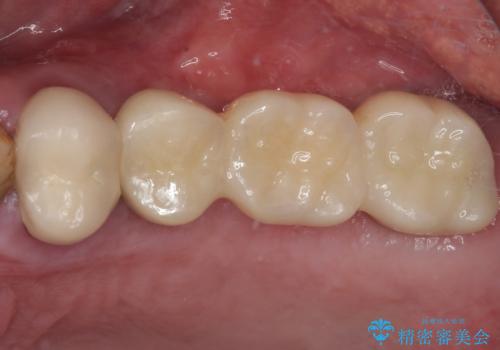

割れてしまった奥歯 抜歯即時埋入インプラントによる短期間治療

いずれの歯も抜歯が必要な状態であり、抜歯即時埋入によるインプラント治療を行うこととしました。

術後にインプラントの安定値を測定し、十分な値が達成された後、速やかにセラミッククラウンにて補綴治療を行うこととしました。